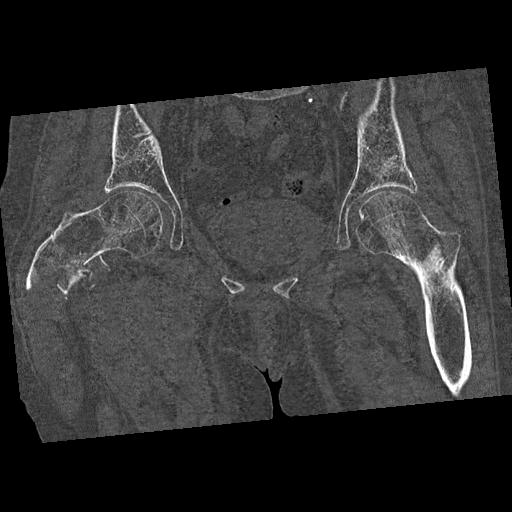

46666 1/28 両股正面+軸と 1/26 右手関節 2R 76歳女性 右転子部骨折

37 1/18 両股正面+軸 1/22 2R 86歳女性 右転子下

91569 3/25 両股正面とラウエン 70歳女性 人工骨頭+バンクーバー